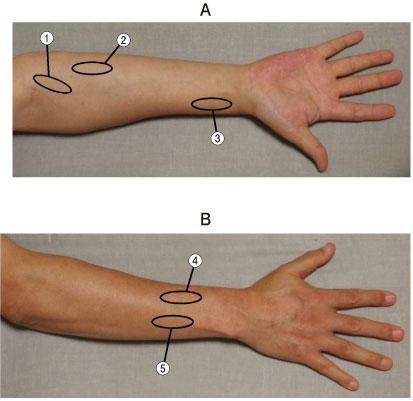

38歳の男性。交通事故による右腕神経叢損傷。肘屈曲を指示したところ、抗重力位では、回外位、中間位、回内位とも自動運動はみられなかった。そのため図のように重力を除いた肢位にしたところ、手関節の伸展、前腕の回内を伴いながら全可動域屈曲した。しかし前腕回外位のままでは肘屈曲ができなかった。この患者の肘屈曲について正しいのはどれか。

1

上腕二頭筋の筋力は2(Poor)である。

2

上腕二頭筋の筋力は3(Fair)である。

3

腕橈骨筋の筋力は3(Fair)である。

4

除重力位での肘屈曲は主として長橈側手根伸筋で行っている。

5

除重力位での肘屈曲は主として橈側手根屈筋で行っている。